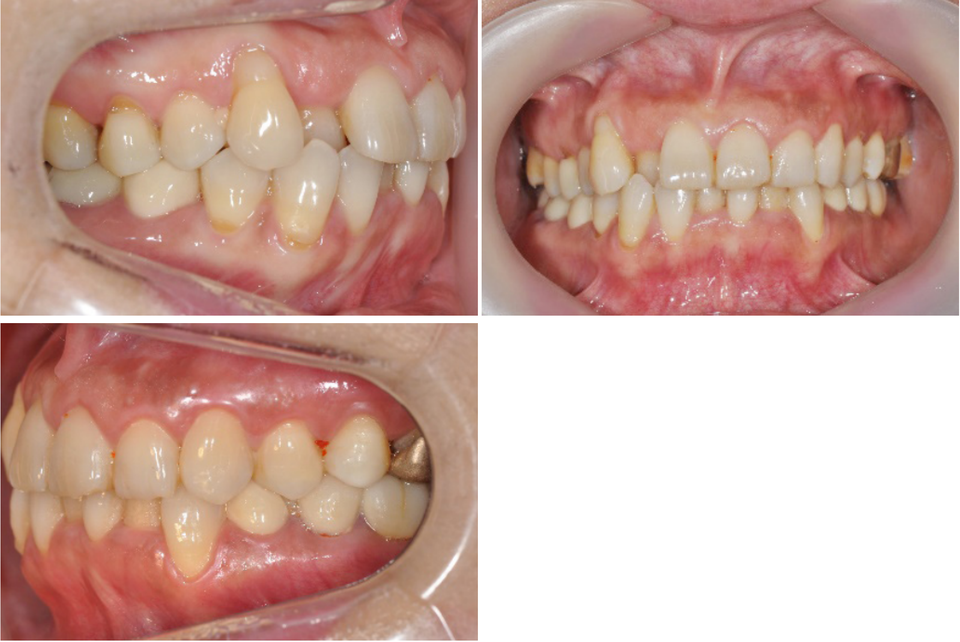

이 환자는 하악우측 제2대구치와 좌측 제1,2대구치가 결손된 환자로 하악 양측 distal cantilever 보철물 하방의 식편압입과 잇몸염증을 주소로 내원하였습니다. 또한 전치부의 crowding을 해결하기 위한 전악교정치료를 원하셨습니다.

하악구치의 cantilever 보철물을 제거하고 temporary crown으로 수복하여 bracket을 부착하였으며 결손부위는 일단 놔둔 상태에서 교정치료를 진행하였습니다.

전치부 decrowding의 영향을 고려하더라도 상하악 전치부의 flare와 동요도가 발생하였는데 이는 대구치부위 posterior support의 부재의 영향이 큽니다.